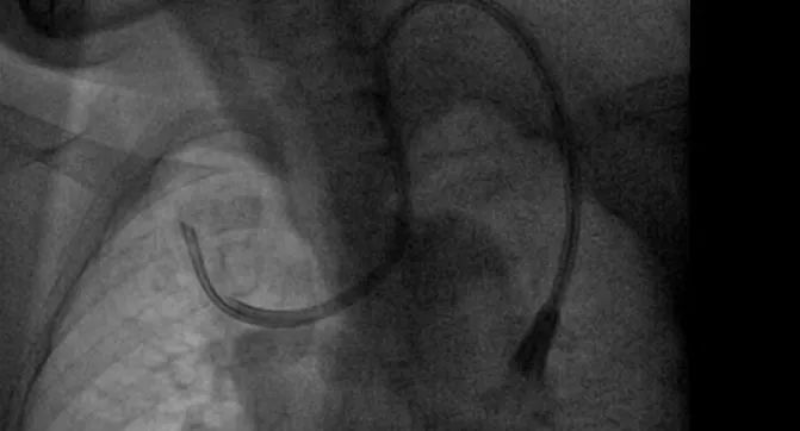

不久前,一位來自河源的患者到惠州市中心人民醫院博羅分院(博羅縣人民醫院)腎內科糾正導管位,這位日常是在當地的醫院進行腹透導管,但總有不適感產生,聽聞惠州市中心人民醫院博羅分院(博羅縣人民醫院)腎內科導管技術優秀,慕名場來求醫。這位病人在當地醫院進行血液透析,但導管流量不足,無法常見透析,到了惠州市中心人民醫院博羅分院(博羅縣人民醫院)就醫以后,腎內科主任吳勇對他進行了全面的檢查,發現該病人體內的導管已經像項鏈一般繞脖一圈,需要立馬糾正。吳勇馬上聯系了惠州市中心人民醫院的手足外科專家進行會診,經討論后對患者進行了球囊擴張術,并重新置入新的導管,術后患者透析順利,返回當地后也能繼續順利透析。該病人對惠州市中心人民醫院博羅分院(博羅縣人民醫院)微創置管導管技術表示了高度的認可,并定期回院復診。

腎內科從2018年分科建立以來,逐步發展壯大。在新一代學科帶頭人吳勇的帶領下,學科克服了人才引留困難、臨床科研基礎薄弱、信息相對閉塞等難題,全科上下積極進取、砥礪前行,在診療技術水平、醫療服務能力、科研教學能力、人才培養及學科影響力等方面取得了重大突破。如前期需要在手術室剖腹進行的腹透置管手術,術后創口大,手術時間久等一系列缺陷,存在許多弊病,吳勇首先對其進行針對指導改良,微創化、輕量化,從經皮穿刺置管術轉變到現在的改良型腹腔鏡下腹透置管術,患者術后半日即可下床自行活動,不會有明顯痛苦。科室還開展了上腔靜脈狹窄球囊擴張術,解決血液透析長期導管帶來的副作用。

2. 血管通路手術、DSA下的疑難置管,上腔靜脈造影+球囊擴張+置管術(靜脈置管、動靜脈內瘺、血液透析長期靜脈導管),彩超引導下經皮靜脈球囊擴張術,是血液透析病人血管通路狹窄治療的利器,可以減少病人痛苦,最大的可能保護病人的血管。